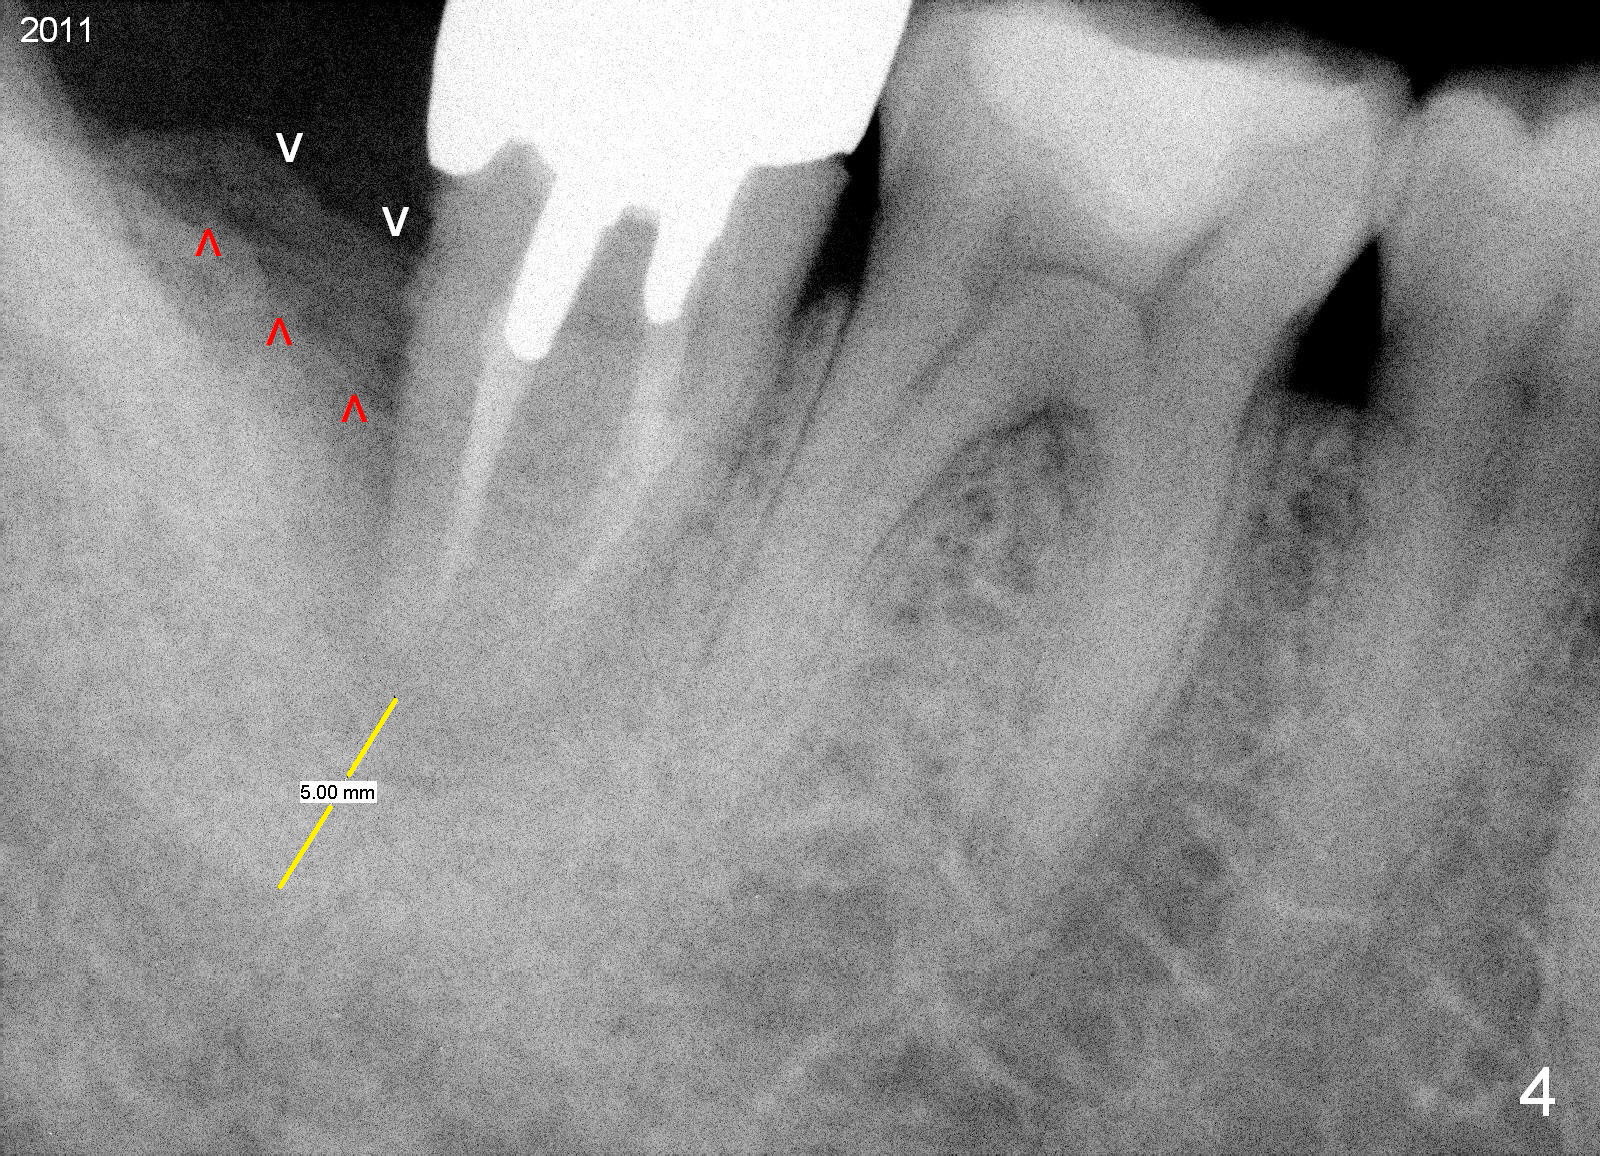

A 44-year-old man has had an asymptomatic distal defect of the tooth #31 for 8 years (Fig.1-5). Recently there is an acute episode of swelling and pain. A fistula develops mesiobucally. Panoramic X-ray films tend to show that the distal defect is deep (Fig.2,5; yellow dashed line: upper border of the Inferior Alveolar Canal). In addition, the distal defect may be not even buccolingually, as indicated by white and red arrowheads in Fig.3,4. Following placement of a 6.9x10 mm bone-level implant, a 7.8x4 (4.5) mm cemented abutment is inserted for try in (Fig.6). When it is fit, it is removed and a cover screw is temporarily placed. A piece of Osteotape (~10x4 mm) is placed distobuccally or distolingually (depending upon which wall is lower). A small amount of bone graft is packed between the most coronal portion of the implant and the Osteotape. The cover screw is then removed and the abutment is re-inserted and tightened by hand. An immediate provisional is fabricated with well-trimmed margin. Reline is done if necessary for securely holding bone graft in place. A new PA is to be taken prior to surgery to determine the extent of the lesion. Photos are taken to show the mesiobuccal fistula. Return to Lower Molar Immediate Implant Xin Wei, DDS, PhD, MS 1st edition 04/12/2015, last revision 05/25/2018